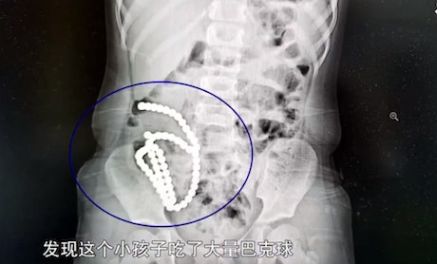

医生为小乐拍摄X光照片后,发现她的胃肠道有一串约1公尺长的白色小点,震惊不已,初时还以为是手串,然而结合早前院方经手的消化道异物病例,怀疑小乐是误吞了磁力珠。

小乐的母亲向医生证实,家里确实有磁力珠,平时都是小乐的哥哥在玩,医生立马心里有数。院方即时进行手术,从小乐腹中取出61颗磁力珠。